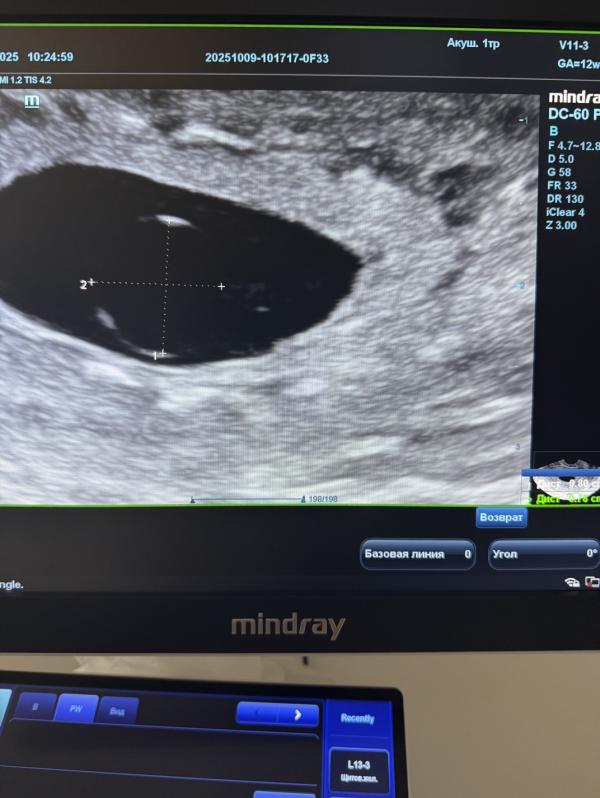

Замершая беременность: как пережить потерю и найти поддержку

Первая долгожданная беременность и замершая …

Девочка заболела и к сожалению сердечко перестало биться💔

Тяжелый диагноз как для пациенток , так и для врача..